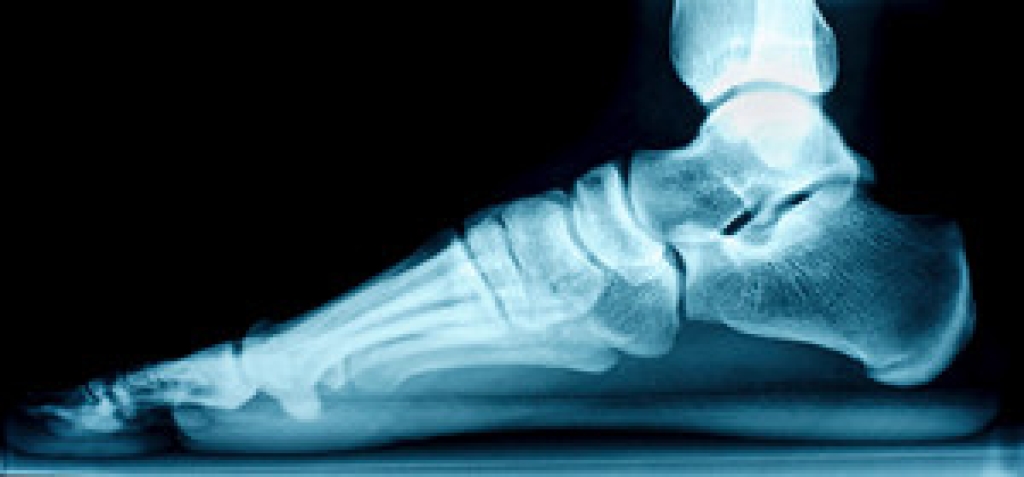

To figure out the cause of foot pain, podiatrists utilize several different methods. This can range from simple visual inspections and sensation tests to X-rays and MRI scans. Prior medical history, family medical history, and any recent physical traumatic events will all be taken into consideration for a proper diagnosis.